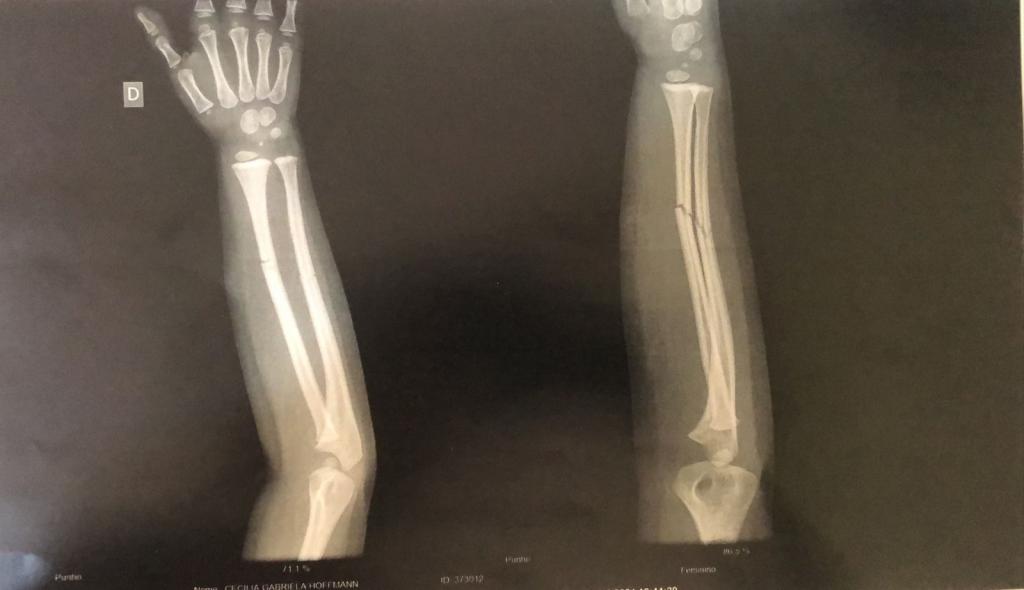

O resultado do exame (imagem acima) apresentou duas fraturas fechadas no braço da criança, que voltou para o hospital Bom Pastor após fazer o Raio-X, e ficou aguardando em um leito a transferência para algum hospital da região a fim de receber atendimento especializado.